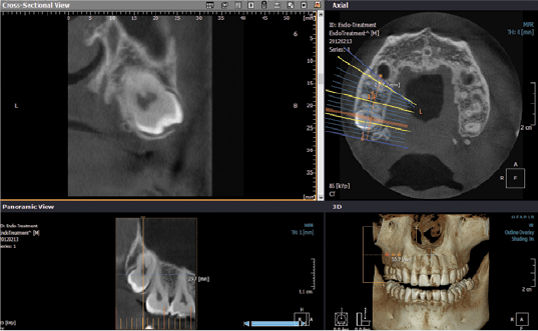

- Pianificazione terapeutica mediante trattamenti implantari

- Programmazione di chirurgia implatare guidata

- Individuazione di fistole, sinusite mascellare odontogena e processi infiammatori periradicolari

- Studio di aree di sclerosi e disomogeneità ossea dei mascellari